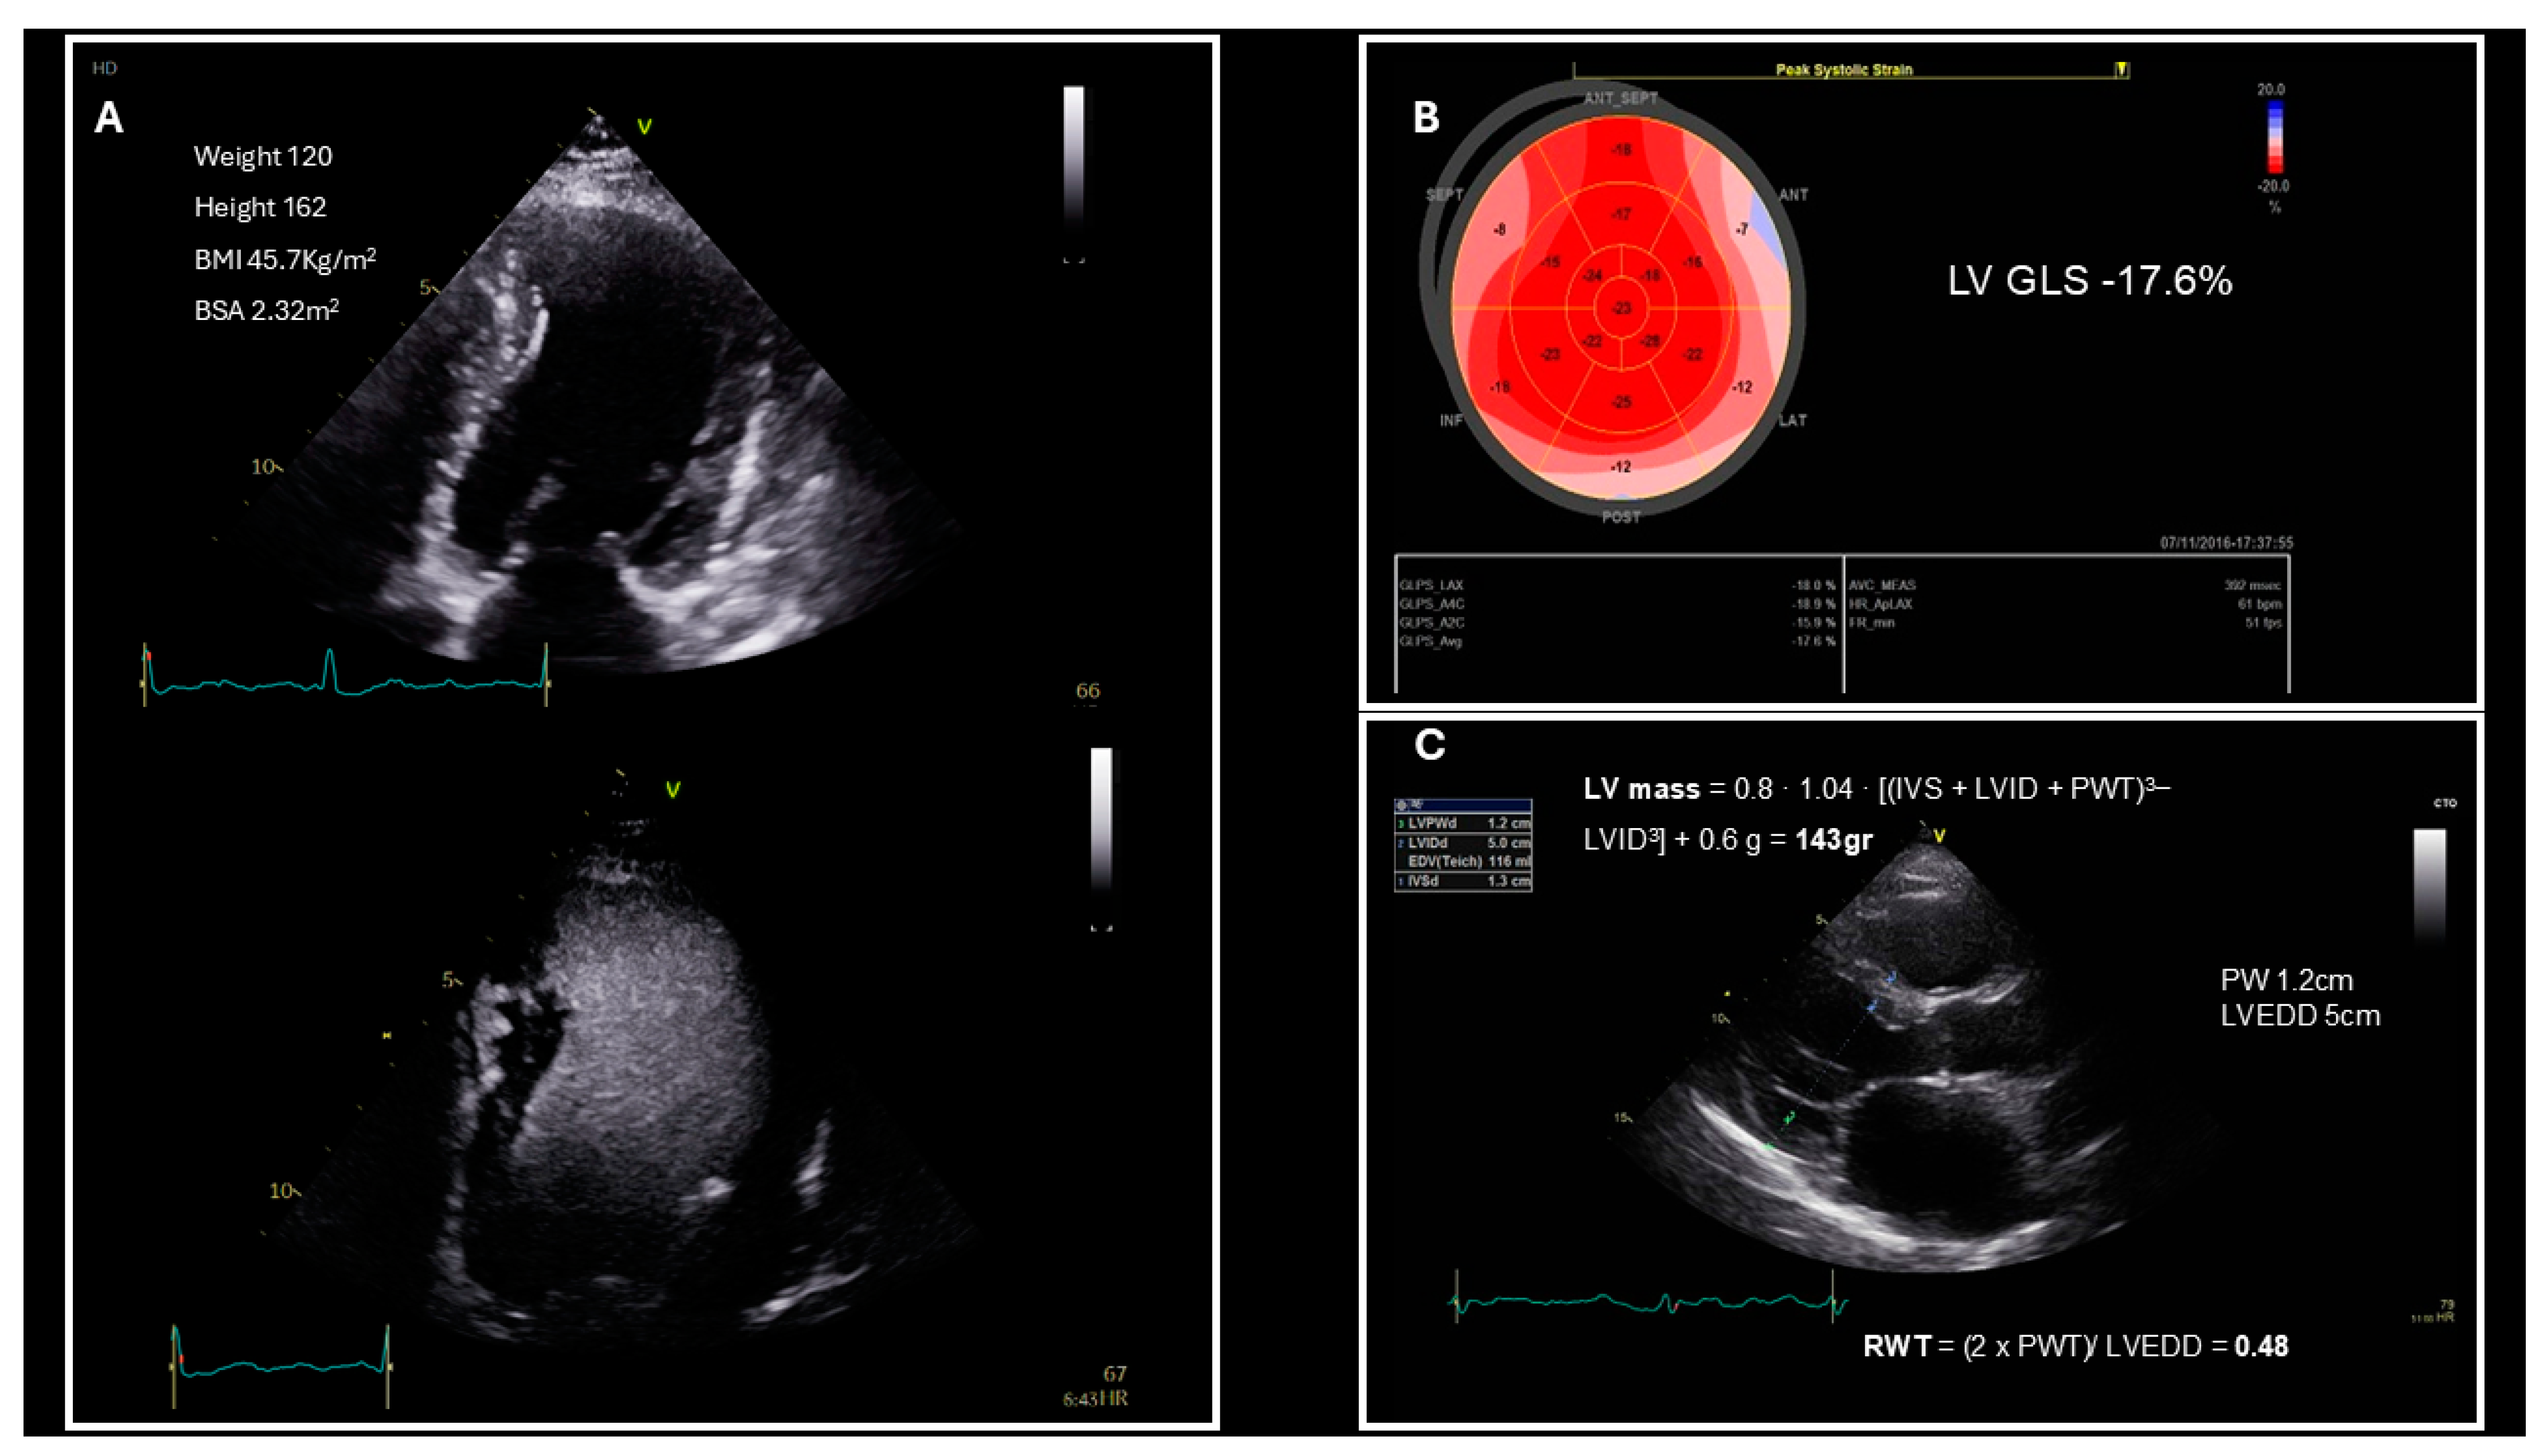

| Left ventricular structure | Left ventricular mass index |

| Relative wall thickness | |

| Left ventricular systolic function | Left ventricular ejection fraction |

| Global longitudinal Strain | |

| Structural | Major | In SR LAVI > 34 mL/m2 (lean)/29 mL/m2 (obese) index to BSA | 2 | |

| LVMI > 50 g/m2.7(men)/>47 g/m2.7(women) index to height + RWT > 0.42 | ||||

| RWT > 0.42 | ||||

| LV wall thickness in the end of diastole ≥ 12 mm | ||||